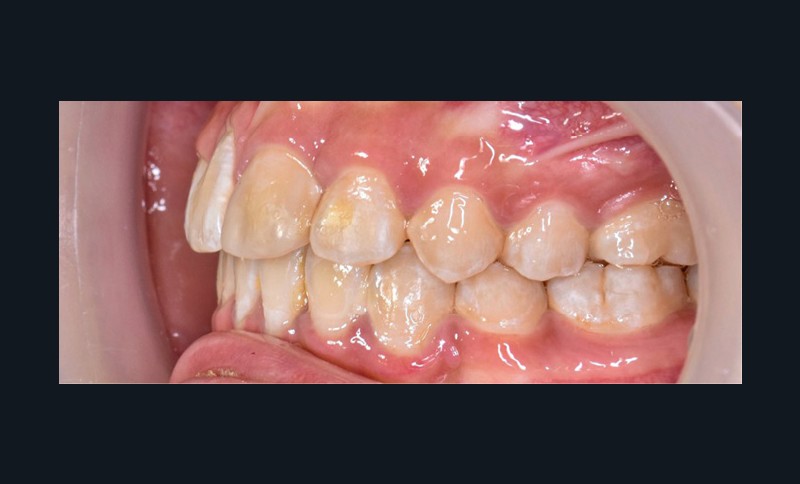

Une patiente âgée de 12 ans se présente en consultation, motivée par la position de son incisive centrale maxillaire, décrite comme « en avant », marquée par une dyschromie et une mobilité de grade 2 selon Muhlemann. L’examen clinique montre l’absence de 23 sur l’arcade, une dysharmonie dents-arcade marquée, un surplomb accentué, et une déviation des milieux inter-incisifs, conséquence du comblement spontané de l’espace de 23. L’ensemble s’inscrit dans un contexte de Classe I d’Angle molaire. L’orthopantomogramme révèle l’inclusion de 23, associée à une résorption radiculaire étendue aux deux tiers de 21. La 22 ne présente aucune altération visible.

La patiente, de profil normodivergent, présente une Classe I squelettique sans troubles fonctionnels (fig. 1-8).